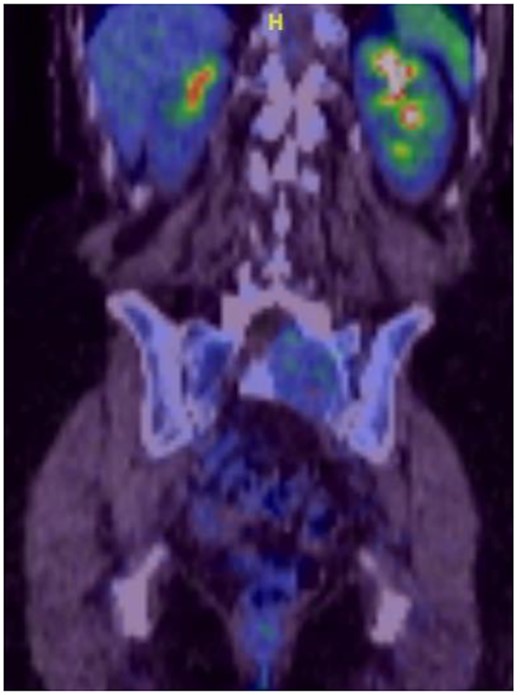

Reviews in July 2019 (with an MRI scan in December 2019) and December 2020 confirmed no neurological deterioration but some increased back and leg pain when standing for some time. A repeat MRI scan confirmed an increase in the size of the lesion (Figs 1 and 2). A biopsy was arranged with a plan for a follow-up surgery. Results of the CT-guided biopsy indicated a diagnosis of metastatic malignant melanoma. Discussions with the patient did not localise any skin lesion responsible for the metastatic deposit, an F18-fluorodeoxyglucose positron emission tomography (18F-FDG PET/CT) scan and a conventional computed axial tomography (CT) scan was organised (April 2021), which revealed sacral destruction and no other deposits in the chest, abdomen and pelvis (Figs 3 and 4). Our patient had a reported SUV of 3.6, indicating a malignant lesion that was then confirmed operatively.